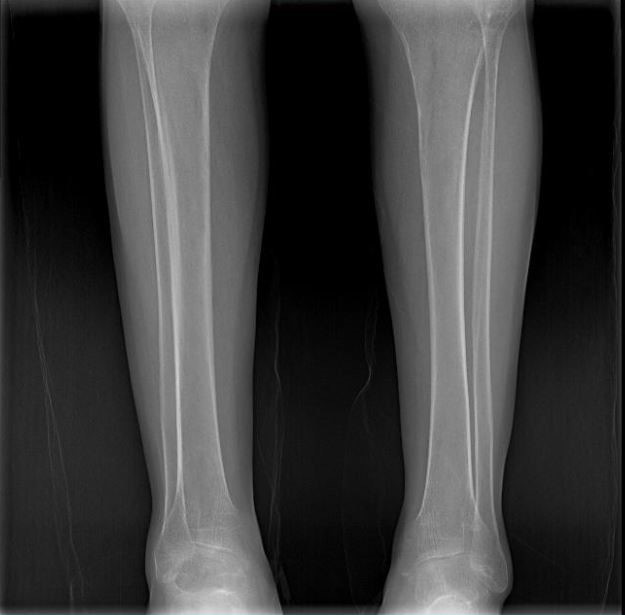

男 70岁

双侧股骨头置换术后

双侧股骨头置换术后复查

通过全景拼接图像可以清晰显示双下肢对比情况,为术后评估提供更多影像学资料。